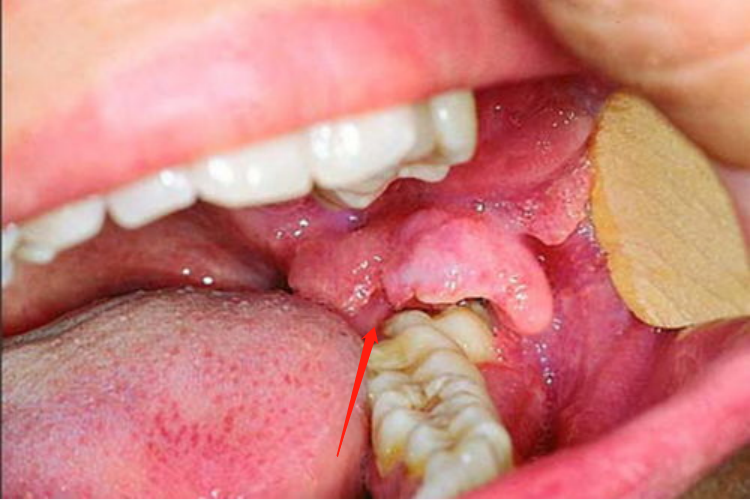

冠周炎:患者可表现为患牙区胀痛不适,当咀嚼、吞咽、开口活动时疼痛加重,口腔检查可见冠周红肿和触痛范围扩大。

冠周炎:是由于正常萌出或阻生的牙齿,在萌出的过程中牙冠周围软组织发生炎症导致。